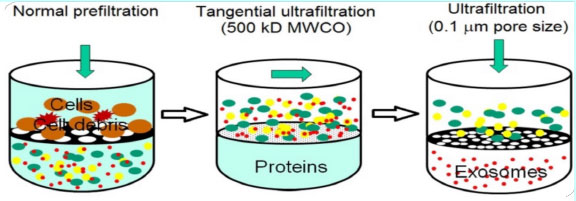

Exosomes are taken from MSC or Mesenchymal stem cells. These stem cells are unique in the human body in that they have the power to differentiate. While all other cells divide and replicate, producing a new cell of precisely the same kind as the original, MSC cells are able to become any type of cell at all.

外泌体取自 MSC 或间充质干细胞。 这些干细胞在人体中是独一无二的,因为它们具有分化的能力。当所有其他细胞分裂和复制产生一个与原始细胞完全相同的新细胞时,MSC 细胞完全能够成为任何类型的细胞。